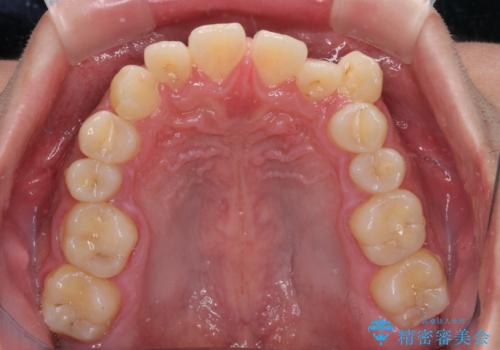

上顎前歯正中の隙間は、舌突出癖によるものと考えられ、舌のトレーニングによる悪習癖改善が必須であるため、徹底するよう指導してから治療を開始することとしました。

舌突出癖が改善されず、なかなか正中の隙間や上下の前歯が接触しなかったために治療が長期化してしまいました。